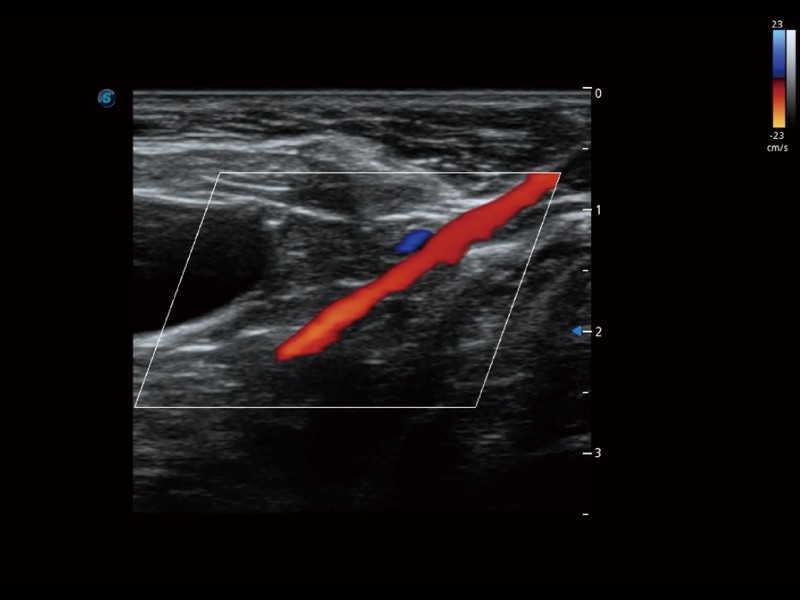

通過(guò)創(chuàng)新的 Matrix E自適應(yīng)濾波器和超長(zhǎng)時(shí)間域算法,極大提升超低速微細(xì)血流的檢出能力,同時(shí)更精準(zhǔn)地濾除軟組織和噪聲信號(hào),為獸用醫(yī)生提供以往無(wú)法通過(guò)常規(guī)血流獲得的疾病診斷信息。

通過(guò)色彩血流和實(shí)時(shí)寬景相結(jié)合,可觀察到完整的靜脈或動(dòng)脈的血流,方便醫(yī)生檢查。實(shí)時(shí)掃查過(guò)程中,如有任何操作失誤也可以很容易地進(jìn)行回掃擦除,而不會(huì)中斷掃查。